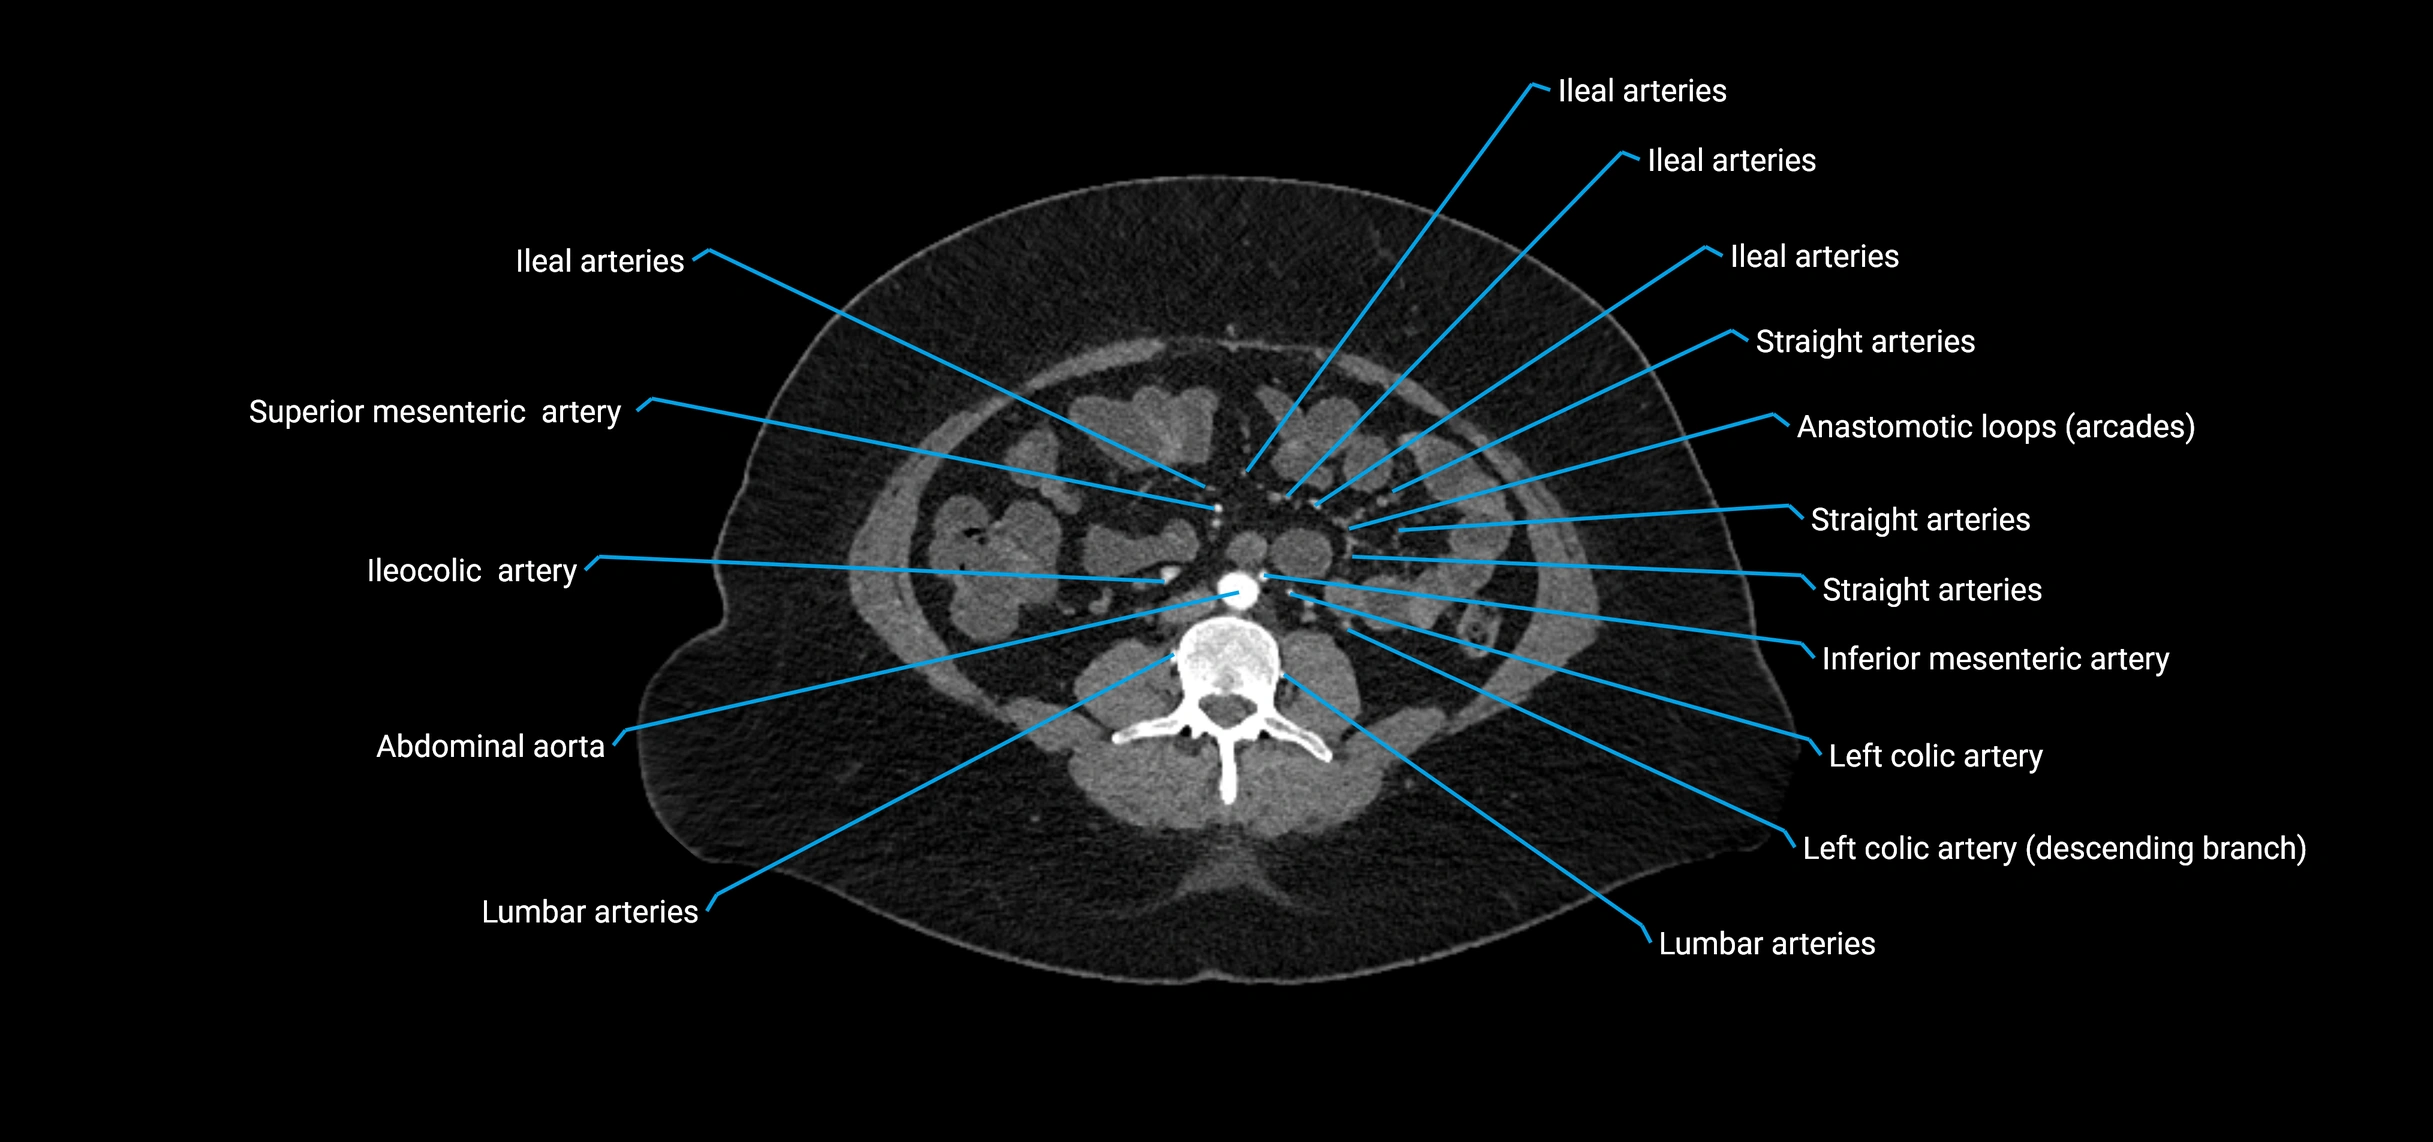

CT images

image

Contrast-enhanced CT (CTA):

• Gold standard for abdominal aortic imaging

• Provides excellent detail of lumen, wall, aneurysm, thrombus, and branch vessels

• Multiplanar and 3D reconstructions help in aneurysm measurement, stent graft planning, and dissection evaluation